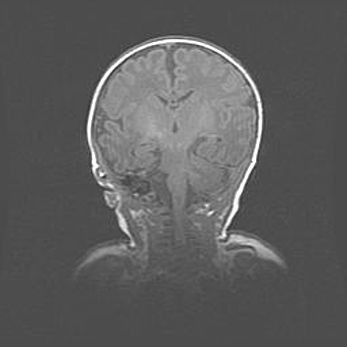

Сообщающаяся гидроцефалия. Кистозная энцефаломаляция головного мозга.

Возраст: 3 месяца 4 дня

Вес: 3100 г

Пол: женский

Окружность головы: 34 см

Срок гестации: 31 неделя

Кистозная энцефаломаляция головного мозга - одна из форм поражения головного мозга в детском возрасте. Характеризуется возникновением множественных и распространённых кист в коре, белом веществе и подкорковых образованиях головного мозга у плодов, новорождённых и детей раннего возраста. Развитие кистозной энцефаломаляции связано с внутриутробной асфиксией и гипотонией, родовой травмой, тромбозом синусов, пороками развития сосудов, инфекциями, сепсисом и другими причинами. Наиболее значимые инфекционные агенты: вирусы простого герпеса, цитомегалии, краснухи, токсоплазмы, энтеробактерии, золотистый стафилококк и другие.